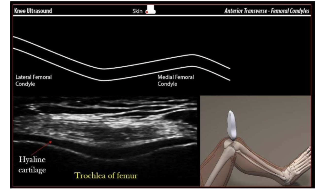

The high frequency linear array transducer

• High frequency 17-5MHz

• Greater resolution

• Superficial structures

• Linear array transducer